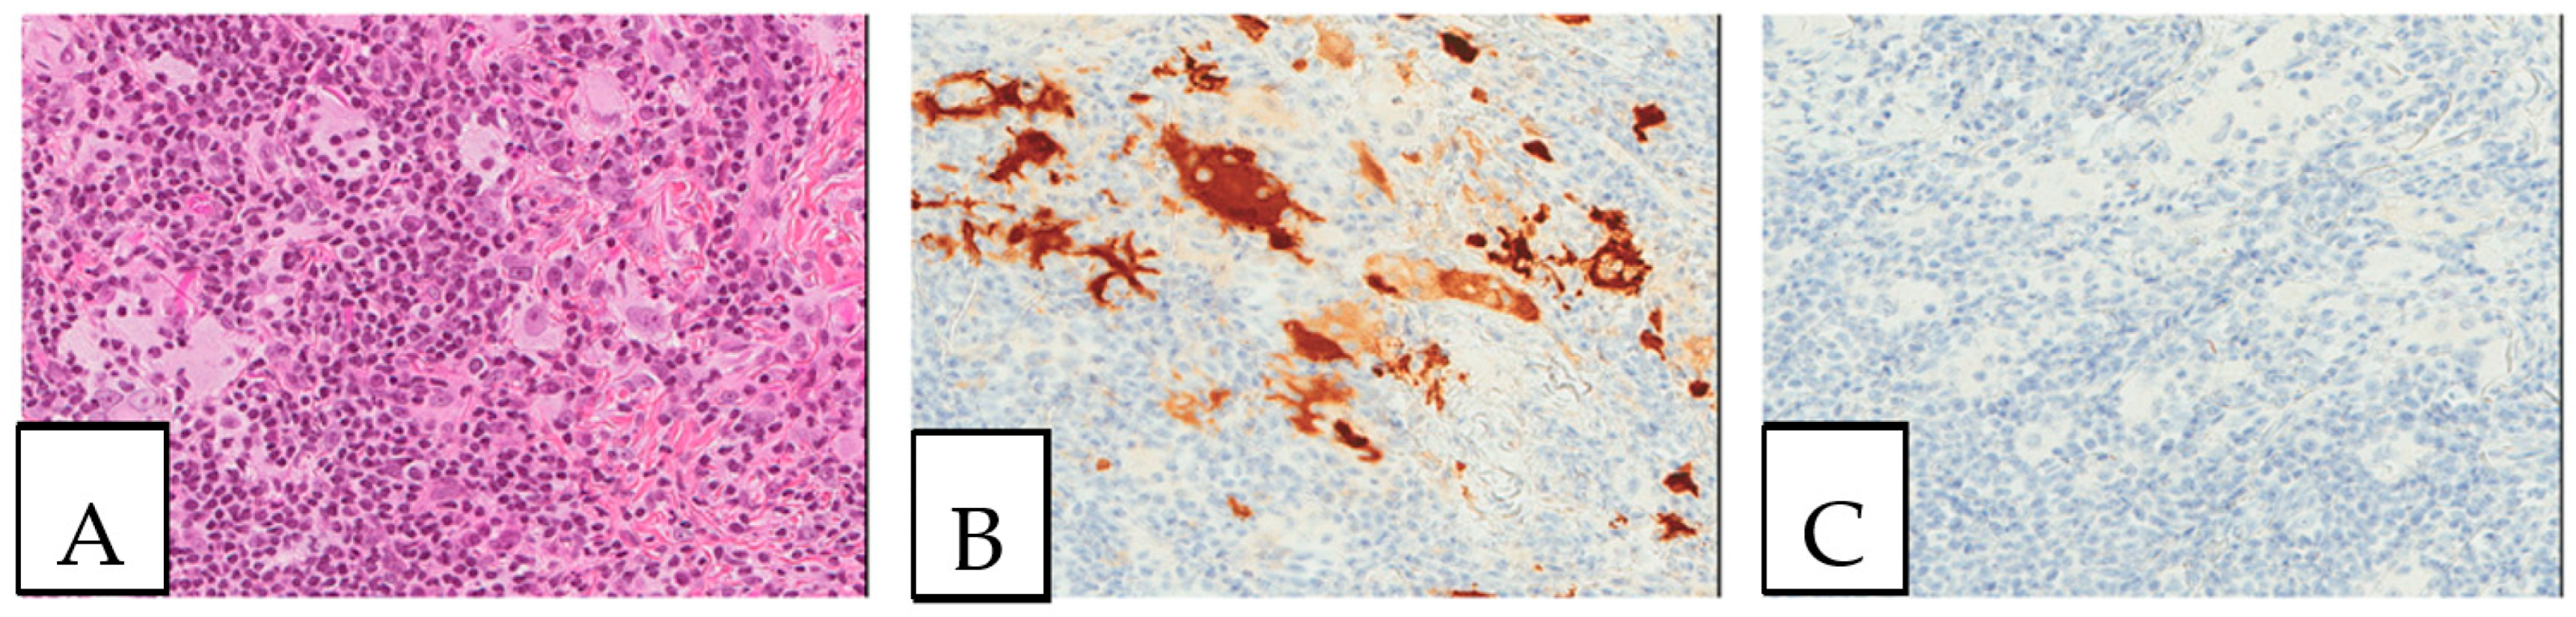

Figure 1. (A,B) Crystal-storing histiocytosis is characterized by an accumulation of histiocytes with intracytoplasmic crystalline inclusions (arrows). (A,B) High magnification of samples from two different cases. (A) A 70-year-old male who presented with abdominal pain, cervical lymphadenopathy, and weight loss with colonic white mucosal elevations on endoscopy. (B) A 50-year-old male with a suspicious lesion of the cavum.

Figure 2. Crystal storing histiocytosis. (A) Morphology of samples affected by crystal-storing histiocytosis, (B) CD68-positive histiocytes, (C) S100-negative lesion. This specimen is from the same patient described in Figure 1 (A) and was taken from a colonic white mucosal elevation.

5. Pathologic Features

Detailed characteristics are presented in Supplementary Table S2. The size of the lesions ranged from 1 mm to 11 cm. A histopathologic examination is considered the gold standard for crystal-storing histiocytosis, as lesions are constantly composed of sheets of histiocytes that are filled up with crystalline needle-shaped to globular eosinophilic cytoplasmic inclusions (Figure 2). These inclusions are rarely accumulated within nearby plasma cells. In renal crystal-storing histiocytosis, eosinophilic cytoplasmic depositions can be seen in the tubular epithelium and in the glomeruli. This material can be positive or negative on PAS stains and typically negative on Congo red, Masson trichrome, acid-fast bacilli, Grocott–Gomori methenamine silver, Perls, Von Kossa, and Sirius red stains. The cells affected by crystal-storing histiocytosis are uniformly positive for anti-CD68 and anti-CD163 on immunohistochemistry, confirming their histiocytic nature. On the other hand, they are negative for anti-S100, anti-CD1a, anti-smooth muscle actin, anti-CD138, anti-langerin, anti-desmin, and anti-myoglobin. Importantly, due to the high clinical association of this disease with the monoclonal lymphoproliferative process with mostly monoclonal IgM kappa light chain restriction, it seems mandatory to investigate for the presence of lymphoma by asking for a lymphoma immunohistochemistry panel including CD20, CD79a, CD3, CD10, CD5, BCL2, BCL6, cyclin D1, CD23, and immunoglobulins light chains, either by immunohistochemistry or by in situ hybridization, as the first step to determine if it is a monoclonal or a polyclonal process. Typically, the crystals react positively to anti-kappa antibodies and negatively to anti-lambda antibodies in most cases of neoplastic crystal-storing histiocytosis. In contrast, crystals in the presence of non-neoplastic polyclonal crystal-storing histiocytosis will be react positively to both anti-kappa antibodies and anti-lambda antibodies. As the commonest accompanied pathology, multiple myeloma presents histologically with sheets or nodules of neoplastic plasma cells on bone marrow biopsy. There is typically an associated reduction in other hematopoietic cell lineages in cases of diffuse involvement. Interestingly, amyloid deposition secondary to the extracellular accumulation of monoclonal immunoglobulins in multiple myeloma can resemble crystal-storing histiocytosis, as it includes cells with an eosinophilic amorphous morphology. Unlike in crystal-storing histiocytosis, the amyloid disposition is positive for Red Congo stain with apple green Birefringent appearance. In addition, the deposition in crystal-storing histiocytosis is mostly within the histiocytes, whereas the amyloid deposition is typically extracellular, vascular, and perivascular. Immunohistochemically, the neoplastic plasma cells are positive for anti-CD138 and anti-MUM1 and present monoclonal immunoglobulin light chain restriction. Extranodal marginal zone lymphoma is characterized by sheets of small lymphocytes that usually reveal a distinct lymphoepithelial lesion in mucosa-associated lymphoid tissue organs such as the stomach. This lesion demonstrates sometimes a plasmacytic differentiation of the tumor cells. The neoplastic lymphocytes are positive for anti-CD20 and anti-BCL2 and negative for anti-CD3, anti-CD5, anti-CD10, and BCL6.